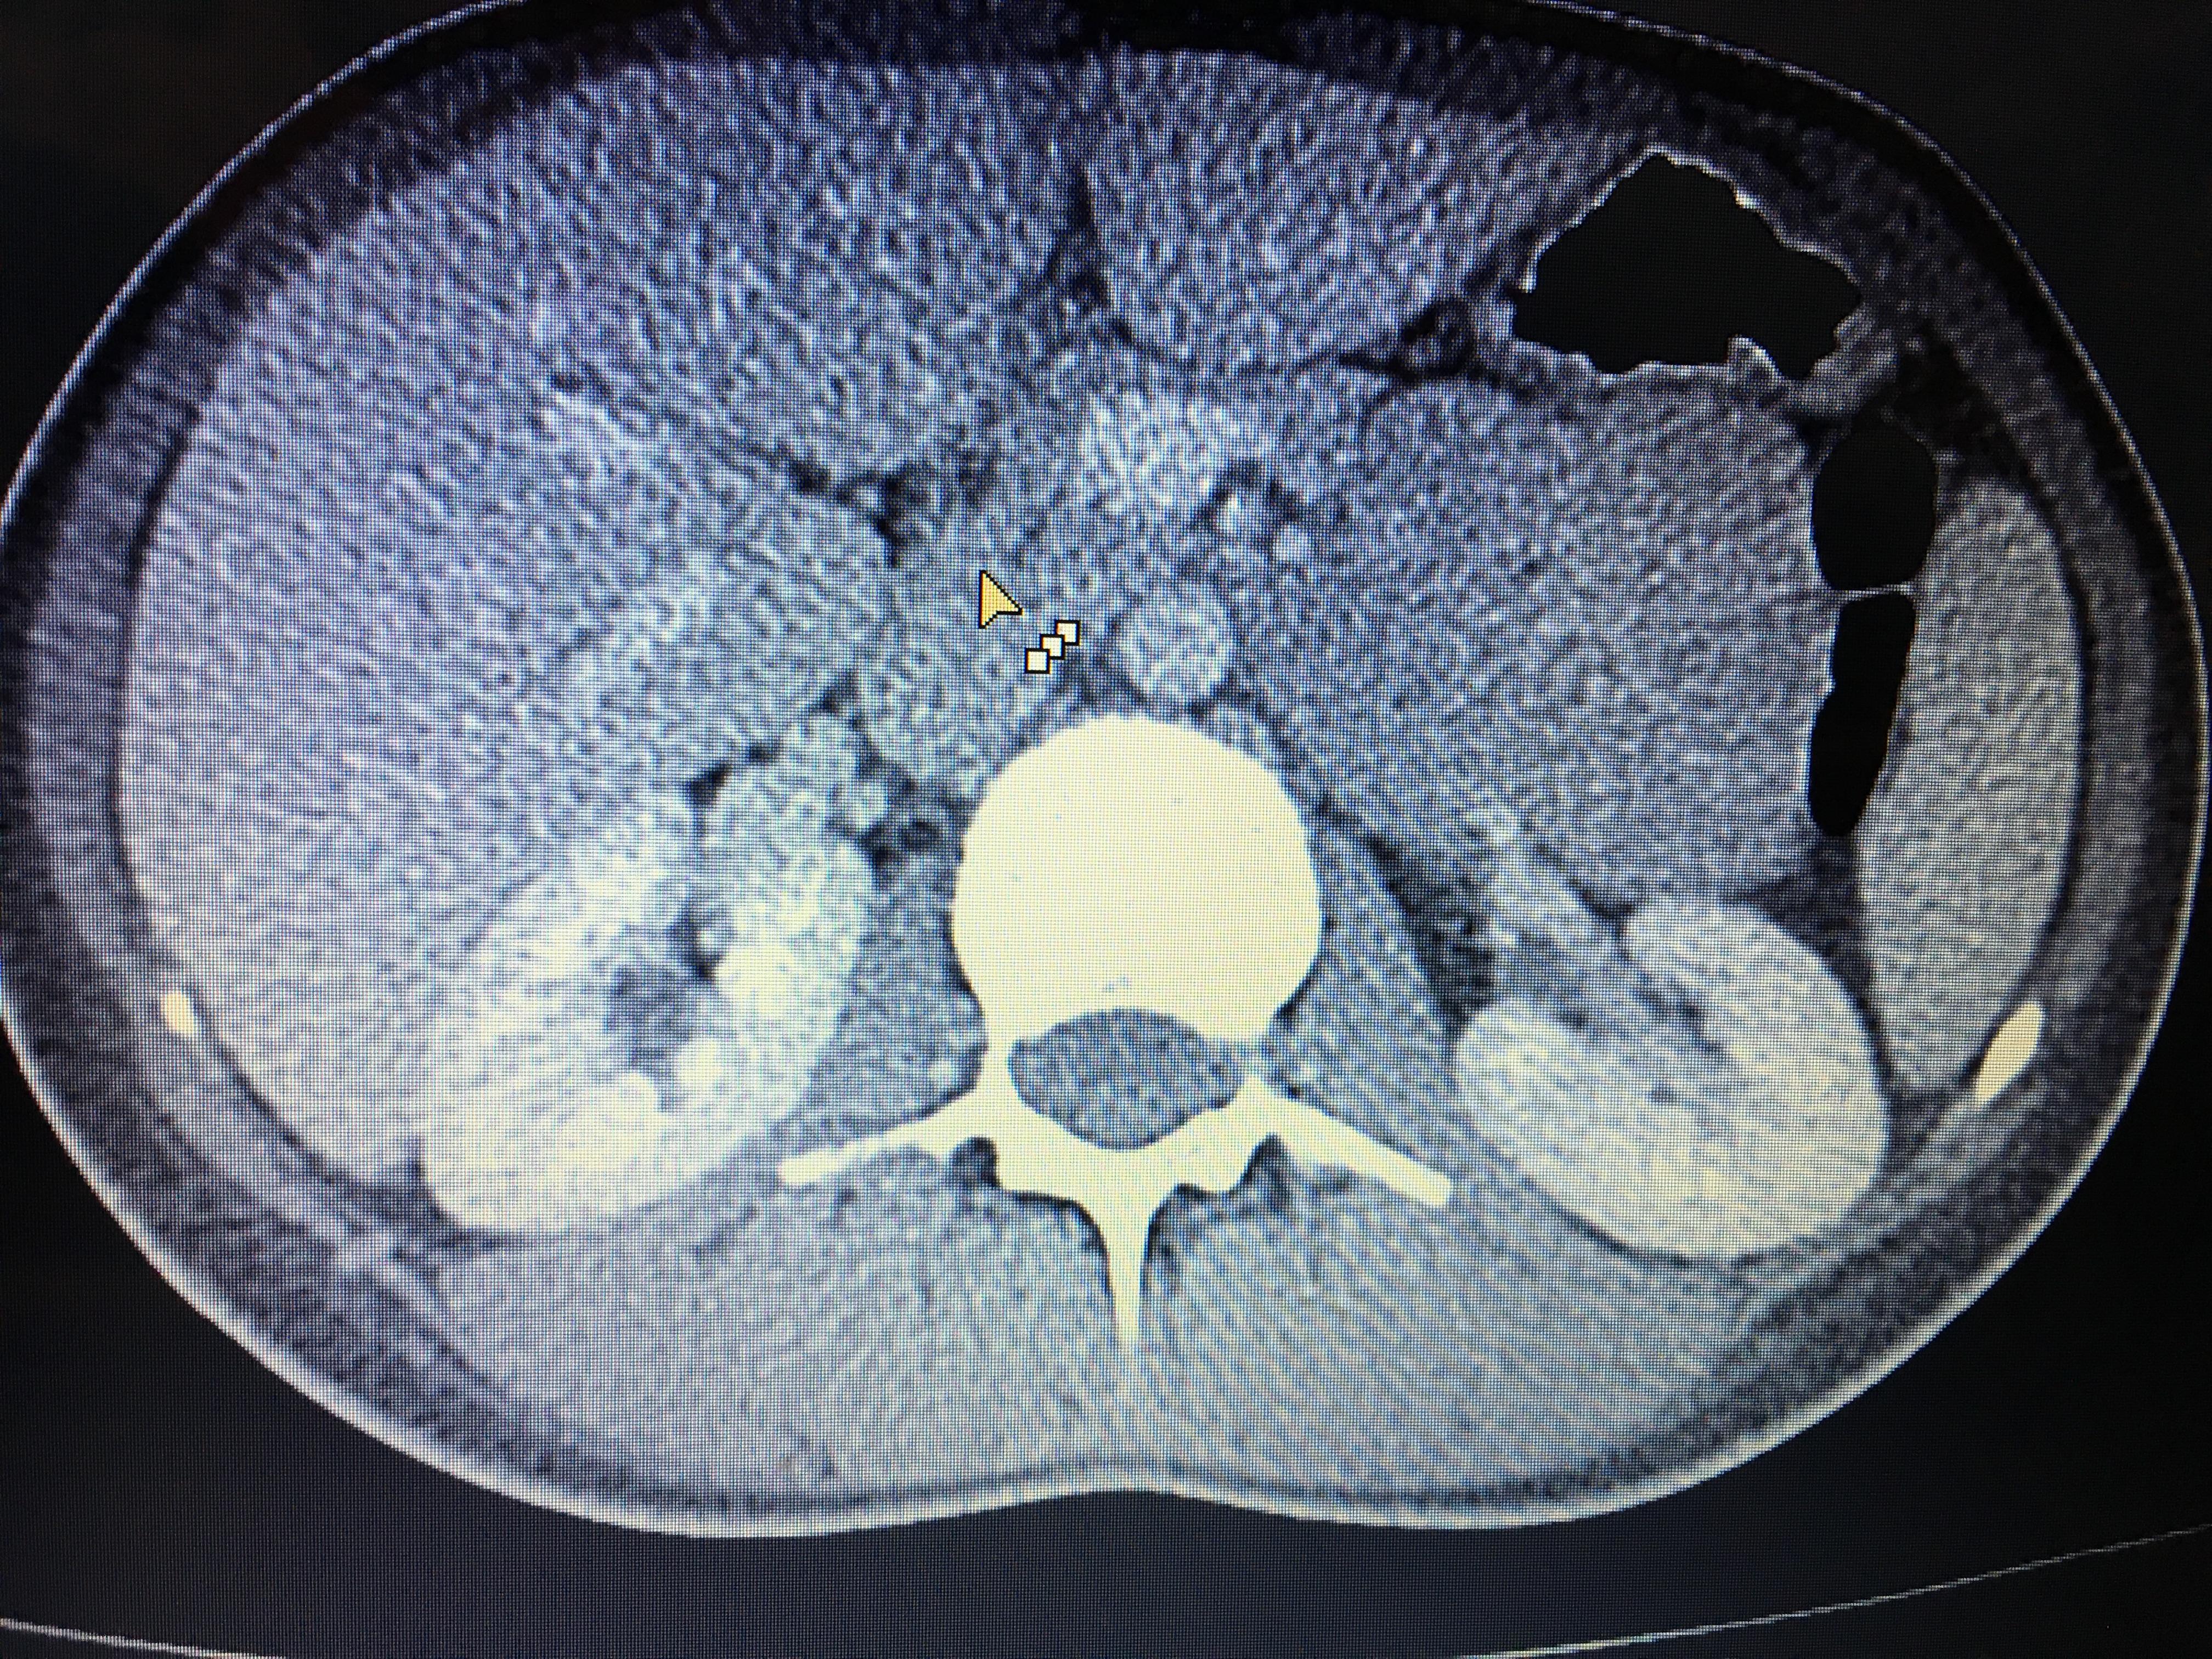

Здравствуйте,помогите, пожалуйста, с расшифровкой кт почек с контрастом. Насколько я поняла, в левой почке маленький камешек. А что за образование в правой почке? Киста с кальцинированной стенкой или камень? Спасибо за ответ!

Здравствуйте! На последнем снимке - больше данных за конкремент. Но при описании снимков должны определяться плотность образования, и нет изображения ни одного фрагмента ни одного из мочеточников. И самих снимков обычно бывает больше. Недостаточно данных для заключения.